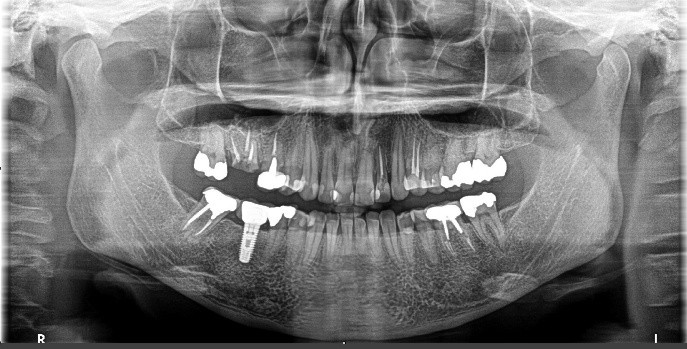

Tooth 4.8 is planned for extraction. Which radiographic findings suggest an increase in the degree of difficulty of the extraction?

13. (Select ONE OR MORE correct answers.)

Tooth 1.8 is planned for surgical extraction. Which radiographic findings suggest an increase in the degree of difficulty of the extraction?

Tooth 2.8 is planned for surgical extraction. Which radiographic findings suggest an increase in the degree of difficulty of the extraction?